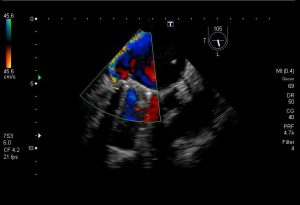

Cierre Endovascular de Leak Paravalvular